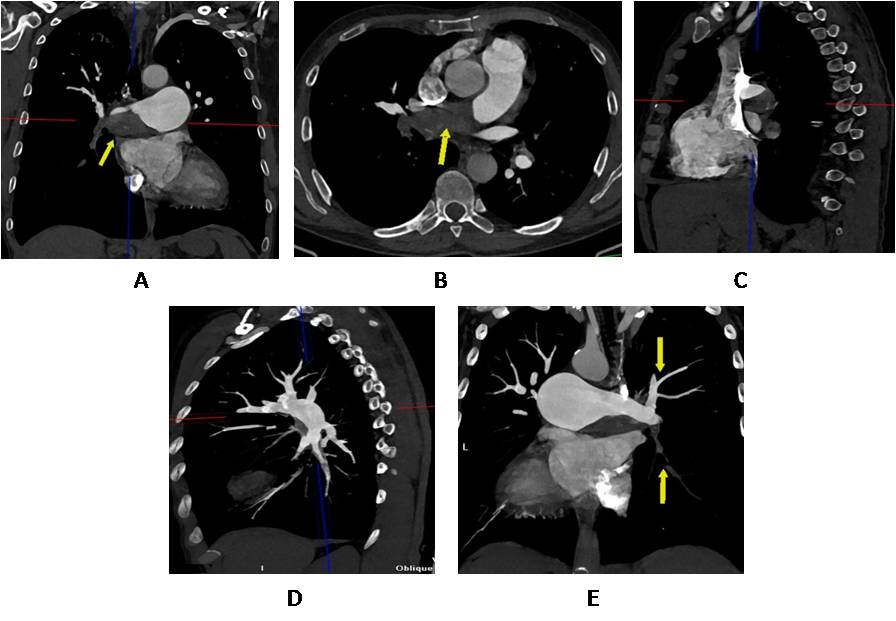

Taking into account the age of the patient, the nature of the underlying and concomitant pathology, the results of laboratory and instrumental research methods, it was decided that it would be expedient to perform selective coronary angiography as part of the preoperative additional examination. According to the latter, no hemodynamically significant stenoses of the coronary arteries were found (Figure 4). As an artifact, a branch of the left coronary artery was found, which forms 2 bronchial arteries of the right lung (Figure 5).

Fig. 4. Angiography results: no hemodynamically significant stenoses were found.

Fig. 5. Angiography results: а branch of the left coronary artery that forms 2 bronchial arteries of the right lung.